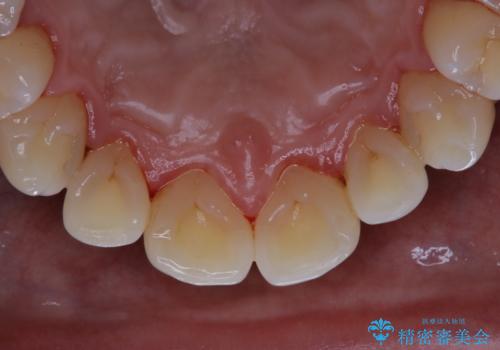

お口全体に、歯垢・歯石が付着していたため、自費クリーニング(PMTC)60分コースを行い、徹底的に除去しました。

終了時

40年ぶりの来院との事で全体的に、古くからの歯垢・歯石が硬く多く付着していたため、自費クリーニング(PMTC)60分1万円+TAXコースを行いました。

よって、歯科衛生士による専門的なクリーニングを定期的に行うことがとても大切です。